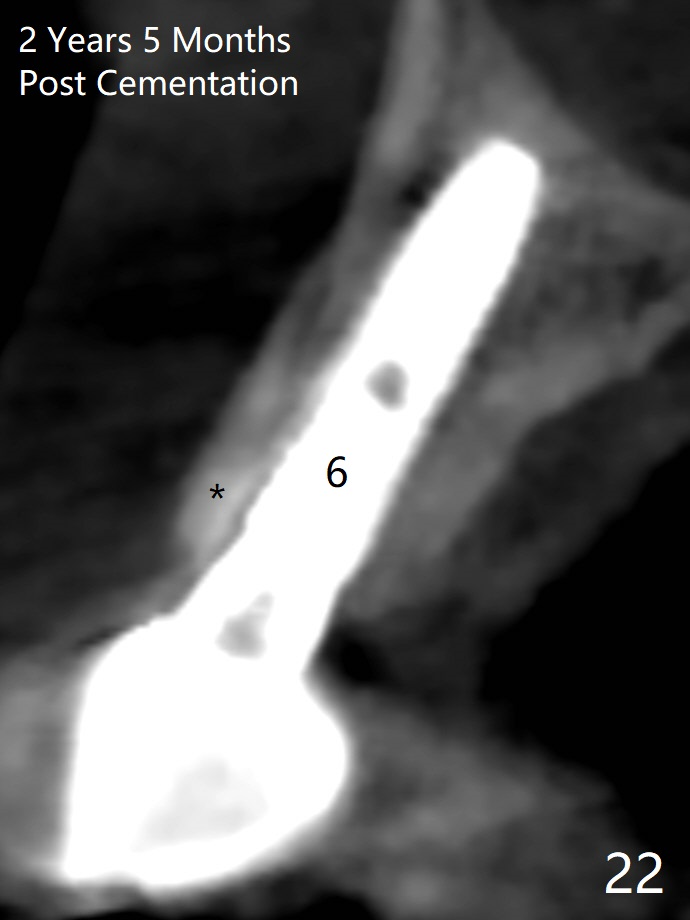

Since the ridge at #7 is ~ 4 mm, a 2.5x14 mm 1-piece implant is placed (Fig.8) after 1.2 mm (Fig.7), and 1.5 mm drills at 12 mm and 2 mm drill at 8 mm. Later the implant is placed deeper (Fig.10). There is no bone loss 7 or 12 months postop, respectively (Fig.11,12). After Diode gingivectomy, there is papillary formation (Fig.13). No provisional is provided after impression (with the abutment torqued at #6) for oral hygiene. With access holes at #6 and 7, crowns are bonded with minimal residual cement (Fig.14 <, which is removed later). There is no hard (Fig.15,16) or soft (Fig.17 *) atrophy 26 months postop, i.e., 13 months post cementation, due to the presence of socket shield (Fig.15 <, as compared to Fig.1). In fact the tooth #8 has mobility and fremitus (short root/poor crown/root ratio, Fig.16); occlusal adjustment is done 13 months post cementation. The crown is dislodged 2 years 1 month post cementation; a prefabricated post is being tried in (Fig.18). There is no atrophy, bone loss or infection at #6 (with socket sheath (*)) or 7 two years 5 months post cementation (Fig.20-27).